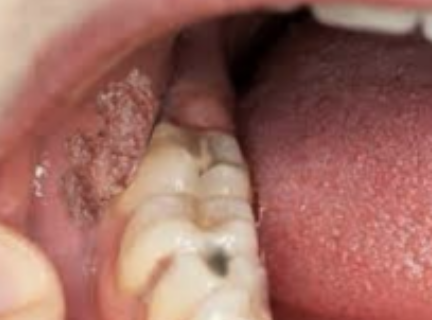

Wat is Hairy leukoplakie?

Dit is een ruwe/gerimpelde afwijking die te zien is aan de longrand. Dit is niet afschraapbaar en komt door een verminderde weerstand. Dit kan veel voorkomen bij mensen met HIV. Er zijn vaak geen klachten, behandeling is vaak niet nodig.